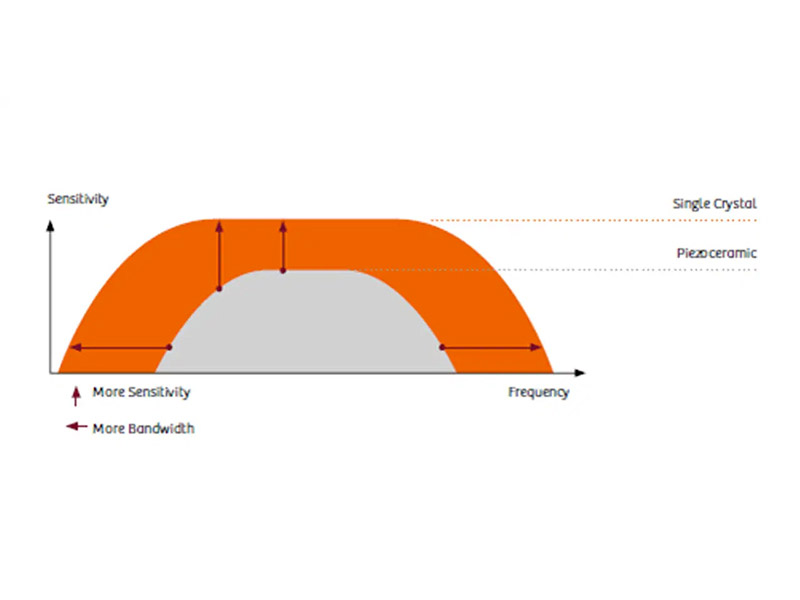

Il design delle sonde Single Crystal di ultima generazione offrono larghezze di banda più ampie per una migliore immagine armonica, una migliore risoluzione assiale ed una maggiore sensibilità per una penetrazione più profonda e immagini più nitide.